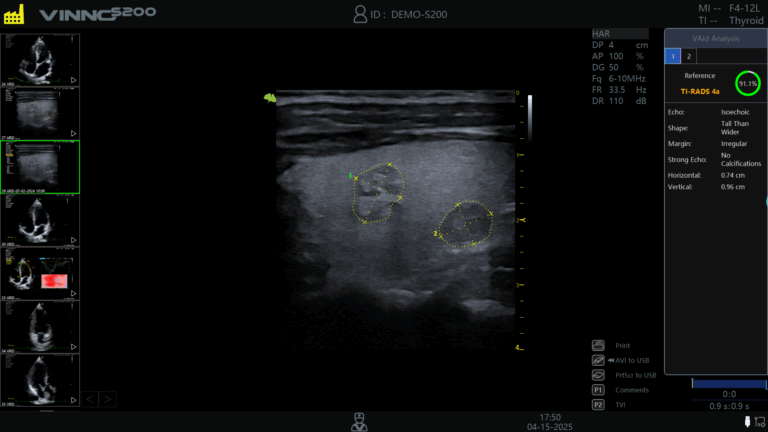

VAid Thyroid – detecteaza automat nodulii tiroidieni, in timp real sau pe imagini stocate, cu incadrare TI-RADS si raportare asistata;